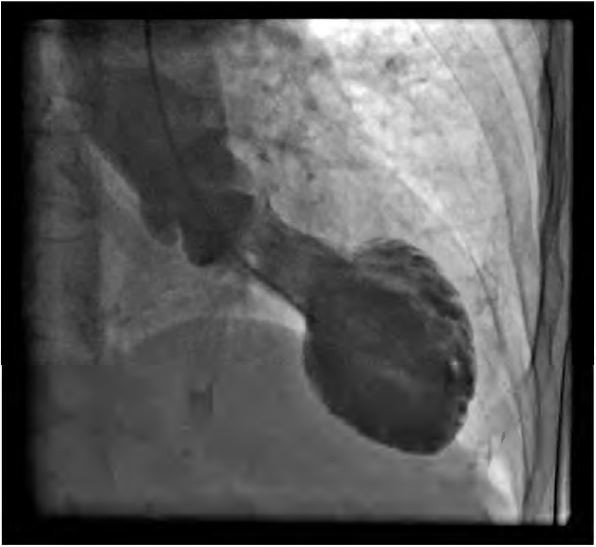

Considere o aspecto de balonamento apical do ventrículo esquerdo, mostrado na ventriculografia abaixo.

Ele é encontrado caracteristicamente